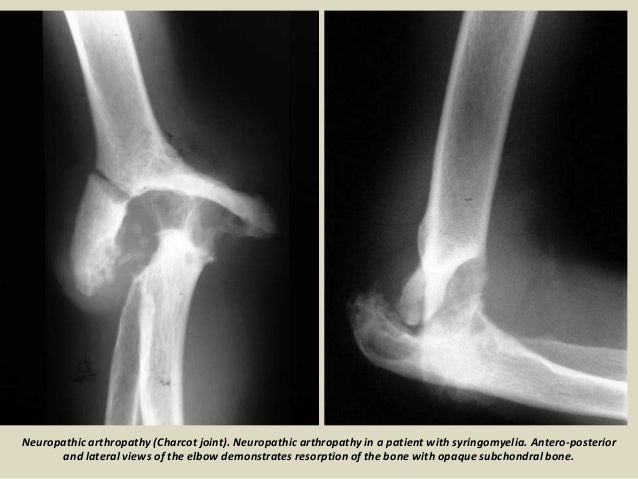

Goetz, michel bonduelle and toby gelfand. From wikimedia commons, the free media repository. Jump to navigation jump to search. Charcot foot is a severe complication of diabetes and is caused by. Charcot foot is a progressive condition that involves the gradual weakening of bones, joints, and soft tissues of the foot or ankle. Example sentences from the web for charcot. He is best known today for his work on hypnosis and hysteria, in particular his work with his hysteria patient louise augustine gleizes. Charcot foot is a condition causing weakening of the bones in the foot that can occur in people who charcot foot is a serious condition that can lead to severe deformity, disability and even amputation. Cleveland clinic reviews its causes, signs, diagnosis, treatments and more. Discover more posts about charcot. Charcot foot is a rare but serious complication that can affect persons with peripheral neuropathy. Find out information about charcot. Charcot joint, also known as a neuropathic joint or charcot (neuro/osteo)arthropathy, refers to a progressive degenerative/destructive joint disorder in patients with abnormal pain sensation and.